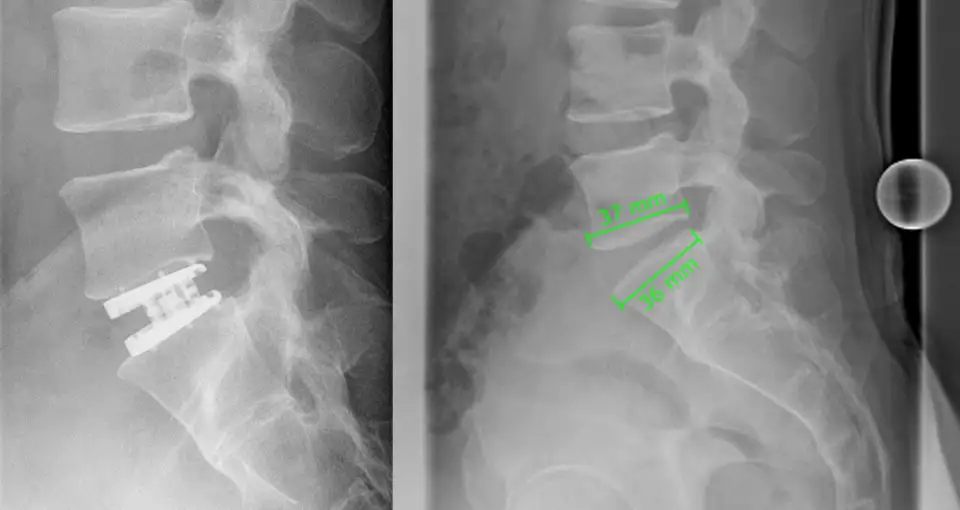

In this multi-hour surgery, the 5th and 6th vertebrae were removed. Cervical vertebrae were removed and replaced with a cage attached to vertebrae 4 and 7. The procedure was uncomplicated and I had almost no pain. For another 6 weeks, I wore a neck brace. My head was completely calm. During this time, I started occupational therapy for the hand and light massage of the neck/shoulder area, which I found very helpful.

For data protection reasons, we have posted a symbol image.